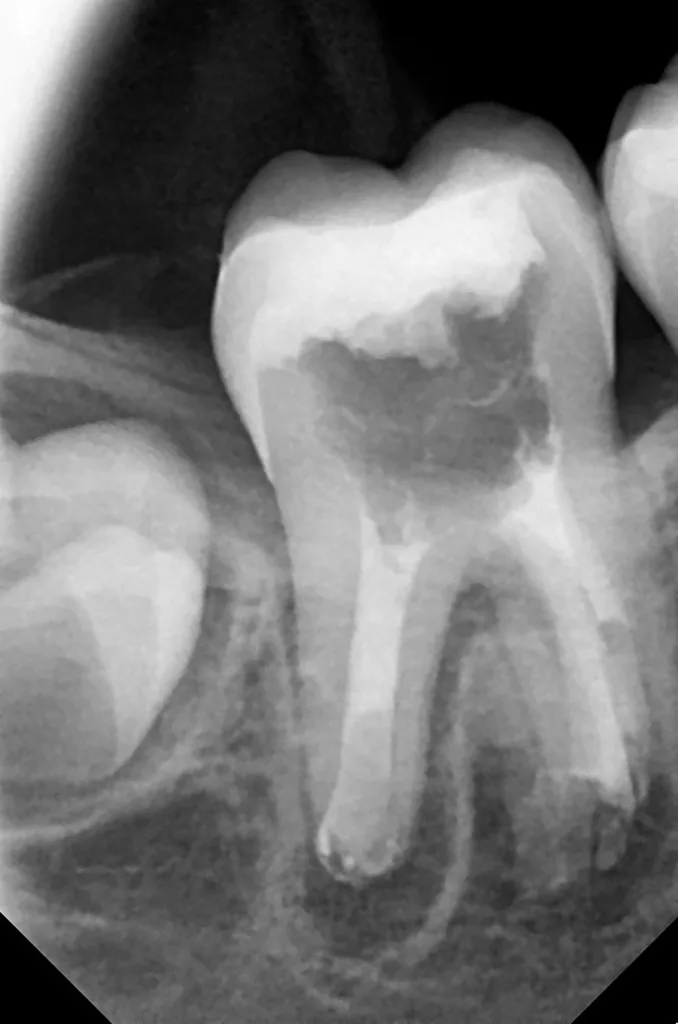

Bei routinemäßigen Röntgenkontrollen ergeben sich manchmal Zufallsbefunde unklarer Genese. So stellt sich beispielsweise bei der Betrachtung der Abbildung 1 die Frage, wie sich ein Zahnhartsubstanzdefekt so schnell entwickeln konnte. Ein weiteres Röntgenbild (Abb. 2), das vor dem Zahndurchbruch aufgenommen wurde, zeigt jedoch, dass es sich in diesem Fall nicht um Karies, sondern um die sogenannte präeruptive intrakoronale Resorption (PEIR) handelt. Für diesen Befund finden sich in der Fachliteratur auch noch andere Bezeichnungen wie „idiopathic external resorption of unerupted permanent teeth“ [1], „intra-follicular caries“ [2], „radiolucent lesions resembling caries“ [3], „occult caries“ [ 4] oder „pre-eruptive caries“ [5].

V. Slabkovskyi, O. Liutikovwährend des Durchbruchs des Zahnes 36.

Das fünfjährige Mädchen stellte sich 2017 zur jährlichen Routinekontrolle vor. Im Rahmen der Untersuchung wurden Röntgenaufnahmen der Milchmolaren gemacht (Abb. 2). Der klinische und radiologische Befund der vor uns früher gelegten Kompositfüllungen war gut, es wurde allerdings eine PEIR an den noch nicht durchgebrochenen ersten bleibenden Molaren festgestellt (Abb. 2). Den Eltern wurde empfohlen, sich unverzüglich bei Beginn des Durchbruchs der ersten Molaren erneut zur Behandlung vorzustellen. Ein Jahr später erschien die junge Patientin schmerzfrei zur Kontrolle. Der Zahn 36 war noch teilweise mit Gingiva bedeckt. Auf einer neuen Röntgenaufnahme (Abb. 1) wurde die PEIR-Läsion mit unveränderter Größe in pulpanahen Bereichen bestätigt (Grad 3 der Läsion nach Seow). Der Zahnschmelz sah intakt aus, es konnte kein pathologischer periapikaler Befund bei den noch nicht ausgewachsenen Zahnwurzeln festgestellt werden. Daraufhin wurden die verschiedenen Behandlungsmöglichkeiten von Fissurenversiegelung bis Vitalerhaltung der Zahnpulpa mit den Eltern des Kindes besprochen.